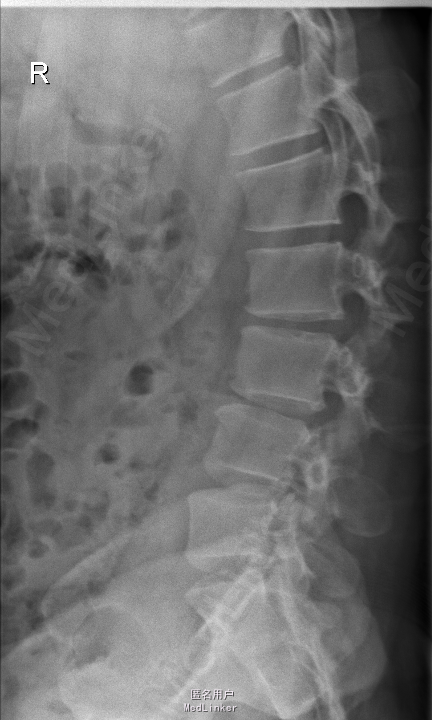

查体:腰部叩痛,腰部活动受限,左侧膝内侧、小腿外侧、内踝、足部感觉减退,右侧小腿、足背感觉减退,屈髋、伸膝、踝背伸肌肌力左侧4级,右侧4-5级,踇背伸、跖屈肌肌力左侧3-4级,右侧4级,双侧膝腱反射+,跟腱反射+,双侧巴氏征阴性,直腿抬高试验左侧40°阳性,右侧阴性。 辅助检查: X-ray:腰椎退行性变,多节段不稳 CT:腰椎间盘突出并椎管狭窄伴钙化,腰2-3,3-4,4-5,腰5骶1 MR:腰椎间盘突出并椎管狭窄,腰2-3,3-4,4-5,腰5骶1 上传受限无法全部上传,见谅

诊断:腰椎间盘突出症并椎管狭窄 处理: 1、完善相关辅助检查,明确诊断,有无手术指证; 2、完善手术评估,有无手术禁忌,手术风险及并发症; 3、在全麻下行腰椎后路多节段减压椎间植骨融合内固定术 4、腰2-3,腰3-4行开窗减压,腰4-5,腰5-骶1行椎间Cage植骨融合

随访: 1、应常规术后1个月、3个月、半年随访; 2、术后患者腰痛较前减轻,下肢麻木感觉较前好转,下肢活动较前有力,屈髋、伸膝、踝背伸肌肌力左侧4级,右侧4-5级,踇背伸、跖屈肌力左侧4级+,右侧4-5级,左侧肢体抬高试验阴性。 讨论: 1、多节段腰椎间盘突出,手术指证把握 2、责任节段的确立,以影像学间盘突出节段为依据,还是联系临床表现?还是术中探查为金标准? 3、多节段间盘突出,开窗髓核VS椎间植骨融合? 4、开窗髓核与椎间植骨融合相结合,如何确定融合节段与开窗节段? 5、多节段内固定,腰椎活动度影响,稳定与腰椎活动功能的平衡?